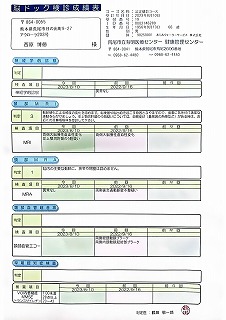

090 脳ドック

2024.18.14 荒尾市民病院 2023.08.10 荒尾市民病院

2024 PDF 2023 PDF

22.9.16 荒尾市民病院